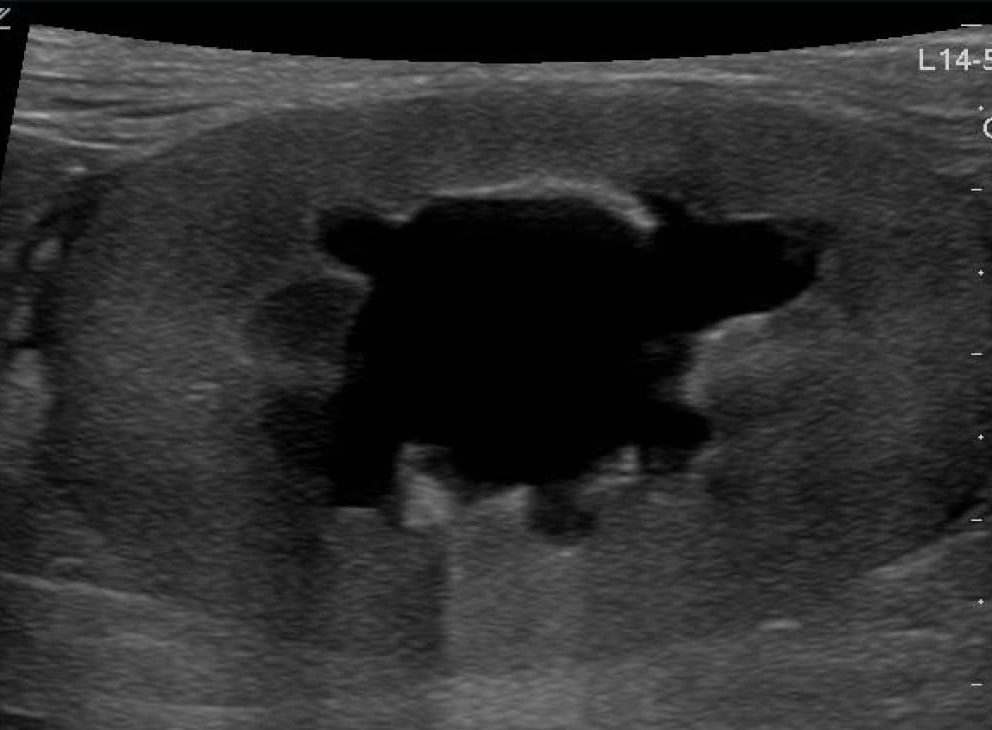

3. Riñón displásico multicístico:

Esta condición se caracteriza por la presencia de múltiples quistes grandes que reemplazan el parénquima renal normal, resultando en una pérdida de la arquitectura renal normal. A diferencia de las enfermedades poliquísticas, el riñón displásico multicístico generalmente afecta solo un riñón y no presenta una diferenciación corticomedular.[1]